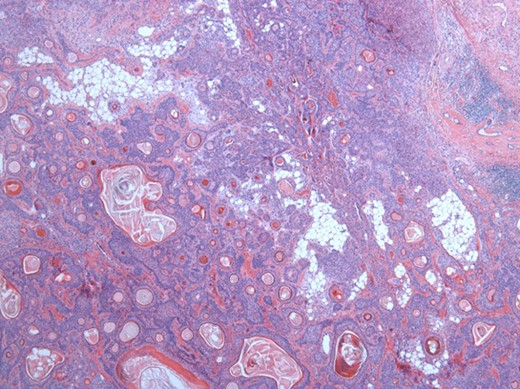

The surgical specimen showed a well-delineated submucosal nodule of 1.7 cm in the greatest diameter, without ulceration. Microscopically, this lesion appeared well defined with a central canal lined by keratinizing squamous epithelium without atypia (Fig. 2). In addition, we found confluent squamous foci with keratinizing centers (Fig. 3). The stroma was mostly fibrous, with occasional adipose and myxoid tissue. Only in the periphery of the lesion did we see a thin layer of normal ductal structures, highlighted by epithelial membrane antigen (EMA) positivity of the luminal cells, with immunochemistry studies (Fig. 4), whereas the other cellular component consisted of myoepithelial cells, highlighted by smooth muscle actin (SMA) and S100 protein (Fig. 5). No mucous secreting cell could be found. Keratin 5/6 and 903 were all positive for the whole specimen. The above-mentioned histopathologic findings helped to conclude the diagnosis of a PA with extensive squamous metaplasia. Margins were negative.

Solid sheets and massive squamous metaplasia with keratinization. Presence of adipose stroma. Hematoxylin and eosin (H&E ×40).